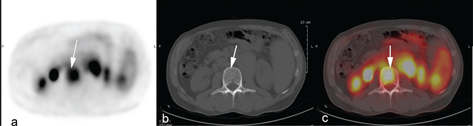

In addition to providing important staging information that determines initial therapy, baseline PET/CT can give additional prognostic information. It has been shown that the metabolic tumor volume (MTV) is an important determinant of treatment outcomes in patients with relapsed/refractory HL (Figure 5). Among 65 transplant-eligible patients, predictors of outcomes were baseline MTV and refractory disease in multivariable analyses. For patients with low MTV (<109.5 cm3) and relapsed disease, the 3-year EFS was 100% (42). MTV is also prognostic in newly diagnosed limited stage HL, as shown in a post-hoc analysis of patients in the EORTC H10 trial. Five-year PFS was 71% in the high-TMTV (>147 cm3) group vs 92% in the low-TMTV group (≤147 cm3) (43). It is likely that further personalized therapies in HL will be represented by combinations of baseline tumor volumes and early response adaptions.

Fig 5

Figure 5. Metabolic tumor volume measurements with volume delineation using the SUV41% thresholding method (a) and SUV2.5 thresholding method (b). The total metabolic tumor volume (including all the lesions) was 91ml with the 41%SUVmax method vs 250ml with SUV>2.5.